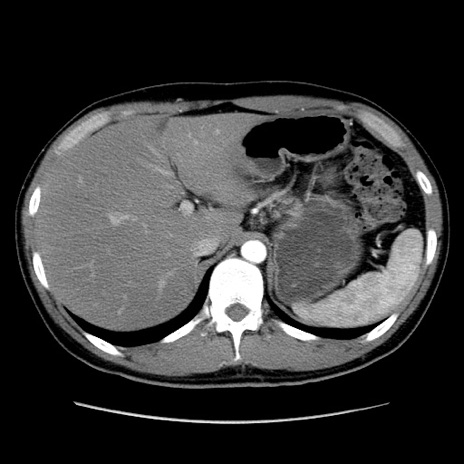

冠状断像

【症例】20歳代 男性

【主訴】心窩部痛

【現病歴】今朝より上腹部痛あり。一旦軽快していたが再度出現したため救急要請。昨日夕に白身の魚を含む刺身を食べた。

【身体所見】BP 136/89mmHg、HR 74/min、BT 37.0℃、腹部:膨満、軟、心窩部に圧痛あり。反跳痛なし、筋性防御なし、腸雑音やや亢進あり。

【データ】WBC 17700、CRP 0.48